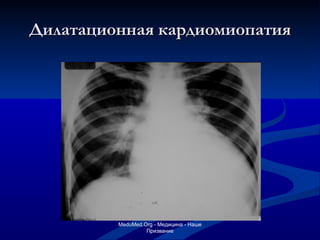

Синдром трапециевидной и овальной конфигурации сердца Врожденные пороки сердца - Болезнь Толочинова-Роже ( низкий дефект межжелудочковой - Синдром Эбштейна (атрезия трехстворчатого клапана) перегородки) Заболевания мышцы сердца - Миокардитический кардиосклероз - Диффузные миокардиты - Дилатационная кардиомиопатия Заболевания перикарда - Экссудативный перикардит - Целомическая киста перикарда

Дилатационная кардиомиопатия MeduMed.Org -  Медицина - Наше Призвание